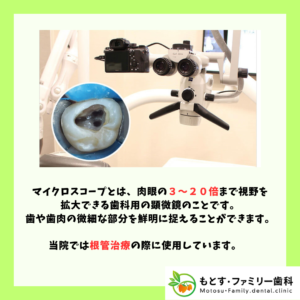

⑦ 精密治療の質が向上する

動画(特にマイクロスコープ映像)を活用すると

- 細部の確認

- 手技の精度向上

→ より精密で再発の少ない治療が可能